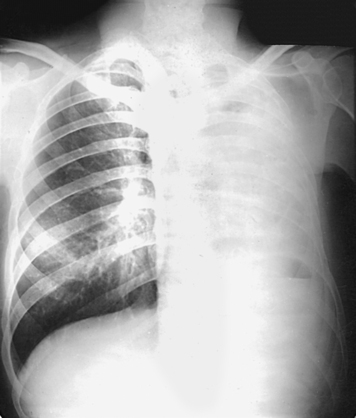

• If a female patient’s breasts are large enough to be superimposed over the lower part of the lung fields, especially the costophrenic angles, ask the patient to pull the breasts upward and laterally. This is especially important when ruling out the presence of fluid. Have the patient hold the breasts in place by leaning against the IR holder (Figs. 10-27 and 10-28).

For certain conditions, such as pneumothorax and the presence of a foreign body, radiographs are sometimes made at the end of full inspiration and expiration (Figs. 10-29 to 10-31). Pneumothorax is shown more clearly on expiration because collapse of the lung is accentuated.